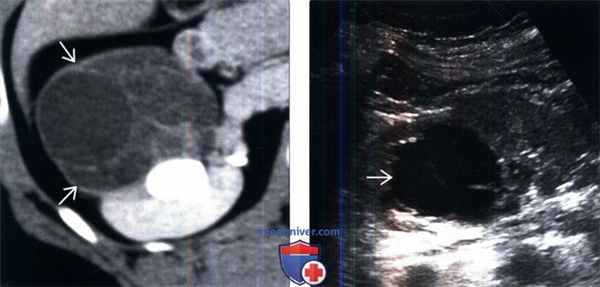

(Слева) КТ с контрастированием, аксиальная проекция: инкапсулированное многокамерное кистозное образование, выступающее в ворота почки, с перегородкой, накапливающей контраст. Наличие капсулы вокруг кисты — отличительная черта, позволяющая отличить мультилокулярную кистозную нефрому от других поликистозных образований почки.

(Справа) На УЗИ в сагиттальной плоскости выявлено покрытое капсулой многокамерное кистозное образование верхнего полюса почки, выступающее непосредственно в почечный синус.